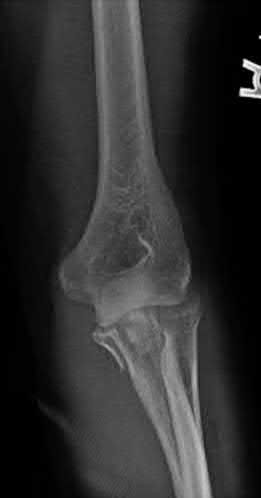

A 15-year-old boy presents with a permeative lytic lesion in the femoral diaphysis with aggressive periosteal reaction ('onion skinning'). Biopsy reveals uniform small round blue cells. Cytogenetic analysis of this tumor will most likely demonstrate which of the following translocations?

The clinical and radiographic description is classic for Ewing sarcoma. The characteristic cytogenetic abnormality is a balanced translocation t(11;22)(q24;q12), which fuses the EWS gene on chromosome 22 with the FLI1 gene on chromosome 11. This is seen in approximately 85-90% of Ewing sarcomas. t(9;22) is the Philadelphia chromosome (CML), t(X;18) is seen in synovial sarcoma, t(2;13) in alveolar rhabdomyosarcoma, and t(12;16) in myxoid liposarcoma.